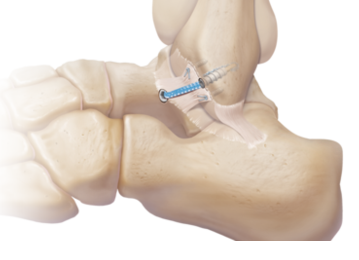

Η διόρθωση του 1ου μεταταρσίου (Βλαισός-κότσι) συγκρατείται με ειδικές βιοσυμβατικές βίδες τιτανίου για μόνιμο αποτέλεσμα χωρίς υποτροπή.

MIS Χειρουργική αντιμετώπιση ρήξης Αχίλλειου Τένοντα

Η ρήξη του Αχίλλειου Τένοντα συνήθως αντιμετωπίζεται χειρουργικά με στόχο την αποκατάσταση της δύναμης και την ελαχιστοποίηση της πιθανότητας νέας ρήξης στο μέλλον.

Η χρήση τεχνικής ελάχιστης παρεμβατικότητας (MIS) με ειδικά εργαλεία μέσα από μικρή τομή εξασφαλίζει πλήρη αποκατάσταση χωρίς παραμονή στην κλινική με ασφάλεια για τον ασθενή.